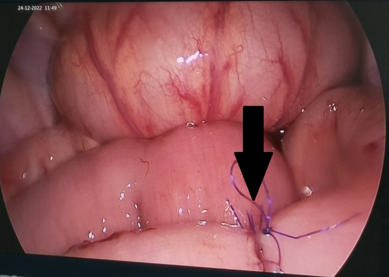

Hình

ảnh nang bạch huyết lớn ( qua mổ nội soi) choán gần hết ổ bụng , đè đẩy các tạng

xung quanh

Nối

lại đoạn ruột sau cắt bỏ khối U để đảm bảo lưu thông đường tiêu hóa